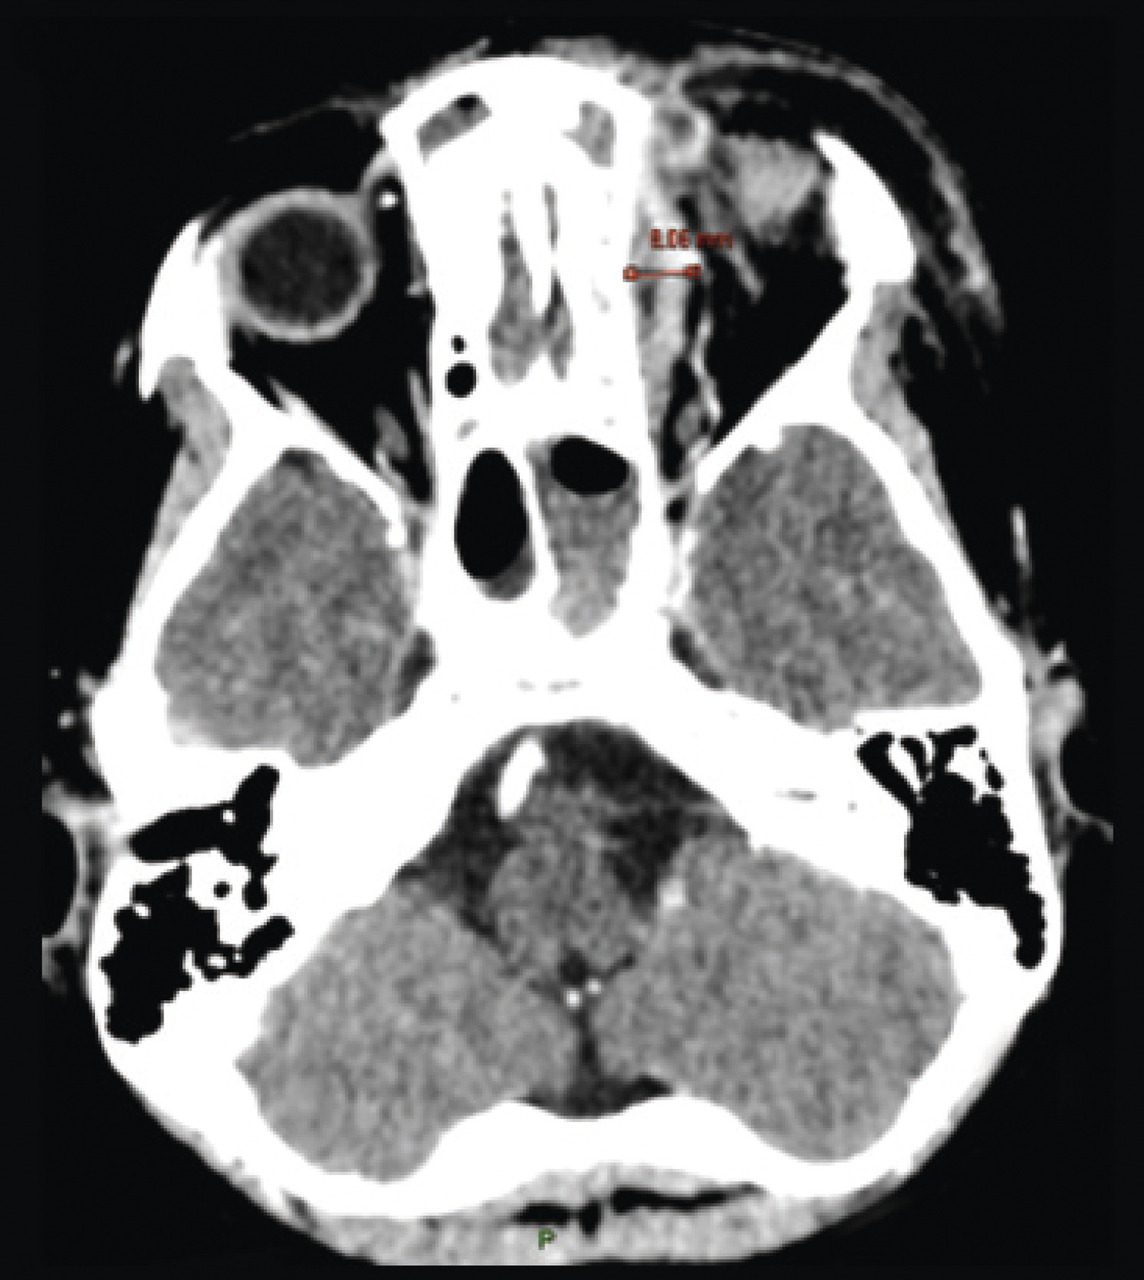

Parmi les formes compliquées, on distingue les complications préseptales touchant le segment antérieur de l’œil et les complications rétroseptales touchant le cône orbitaire. Les complications préseptales sont les plus fréquentes et de meilleur pronostic que les complications rétroseptales. La tomodensitométrie avec injection de produit de contraste permet de les distinguer au mieux. Les trois principales complications rétroseptales correspondent à une diffusion régionale de l’infection :

• forme collectée périorbitaire, définie par la présence d’une collection entre la paroi interne d’orbite et la péri­orbite (fig. 2), suspectée devant l’apparition d’une exophtalmie douloureuse, avec parfois une discrète limitation de la mobilité oculaire ;